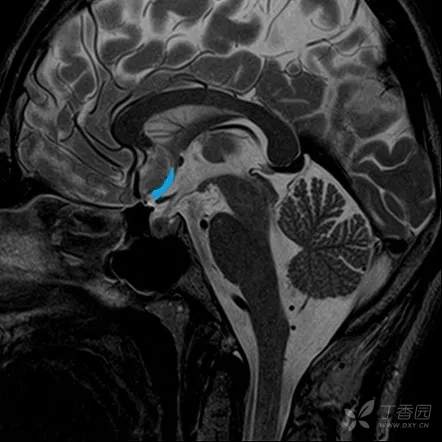

鞍上池

位置与组成

鞍上池 suprasellar cistern 为CT 和MRI 等影像学用语。鞍上池位于蝶鞍上方,是交叉池、脚间池或桥池在轴位扫描时的共同显影。

1. 交叉池 chiasmatic cistern 位于视交叉周围,外界是颈内动脉,前方有大脑前动脉和前交通动脉。

2. 脚间池 interpeduncular cistern 位于视交叉后方、脚间窝前方,内有动眼神经、大脑后动脉水平段等。

3. 桥池 pontine cistern 位于斜坡与脑桥基底部之间,内有基底动脉,向两侧与脑桥小脑角池延续。

类型

因扫描层面的不同和年龄与个体差异的影响,鞍上池可分为六角形、五角形和四角形等不同形态,分别阐述如下。

- 六角形鞍上池

- 如CT 扫描层面偏高或头偏前倾,则出现六角形鞍上池。六角形鞍上池由交叉池和脚间池组成,包括一个前角、一对前外侧角、一对后外侧角和一个后角。前角伸向两大脑额叶之间,并延续为大脑纵裂池;前外侧角伸向额、颞叶之间,延续为大脑外侧窝池;后外侧角伸向大脑与中脑之间,延续为环池;后角则为脚间池。在前角和前外侧角之间的鞍上池前方为额叶的直回;在前、后外侧角之间的鞍上池侧方为颇叶的钩;在后外侧角和后角之间的鞍上池后方为中脑大脑脚底。六角形鞍上池内主要有视交叉或视束、颈内动脉、漏斗或垂体柄、乳头体、动眼神经和大脑后动脉水平段。

- 五角形鞍上池

- CT 扫描时,头若呈后伸位,则出现五角形鞍上池。五角形鞍上池由交叉池和桥池组成,后方为脑桥基底部,其他毗邻关系同六角形鞍上池。池内主要有视交叉、颈内动脉、垂体柄、鞍背和基底动脉末端等。

- 四角形鞍上池

- 如扫描层面较高,因缺少后外侧角(大脑脚池不显影),则出现四角形鞍上池。池内主要有视交叉和视束、漏斗和乳头体。四角形鞍上池的毗邻:前是额叶直回,后为脚间窝,两侧为钩。